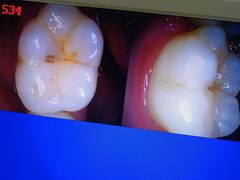

• 土豆口腔(凤凰北总店)

• -土豆口腔(凤凰北总店)

金文博_5274 | 24-11-01